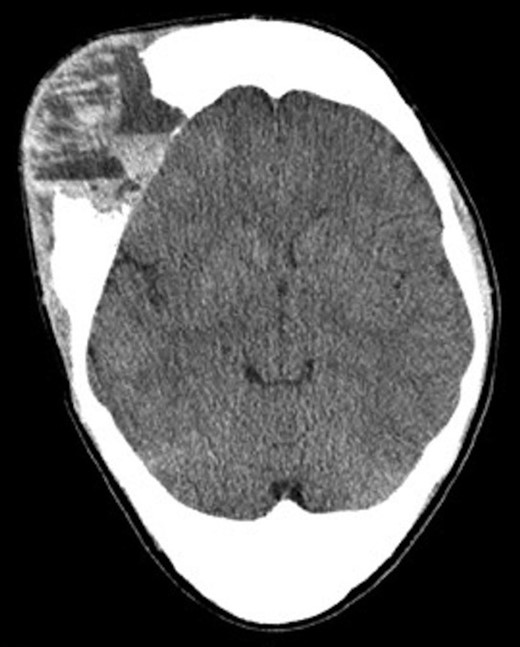

A computed tomography (CT) scan of the head 1-month after initial presentation revealed an aggressively appearing 5 cm × 5 cm soft tissue mass that was lytic and expansile involving the right frontal bone (Fig. 1). The lesion also involved the occipital bone with extension into the central skull base, nasal cavity and right nasal bone. Given the evidence of bone expansion and ground-glass appearance involving the calvarium, diagnosis was determined to be FD. Two weeks later, MRI studies revealed an aggressively enhancing 11 cm × 8 cm soft tissue mass with loculated fluid levels in the right frontal bone (Fig. 2). Extensive destruction of the outer table of the skull was noted with severe thinning of the skull inner table. Findings were thought to be consistent with ABC formation. Extensive bony involvement was noted primarily in the anterior and central skull base, but also in the occipital calvarium. Extension to the right zygoma and orbital walls with narrowing of the bony orbit was also visualized.